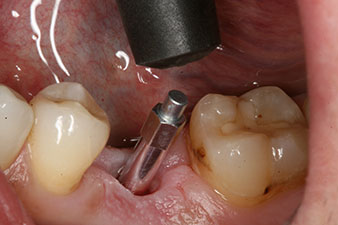

Имплантът е поставен както е планирано след цялостно отстраняване на гранулационната тъкан (blueSky, bredent).

Въртящият момент, използван за машинно-задвижвано поставяне, е 43 Ncm. Освен това, след завинтване на измервателния щифт (SmartPeg), специално пригоден за импланта, стойността на ISQ се измерва със сондата на W&H Osstell ISQ модула.

Този модул е допълнителна екстра към Implantmed на W&H и е закачен към имплантологичния мотор (виж фиг. 11). Липсата на ISQ стойност непосредствено след поставянето е 64 оровестибуларно и 68 мезиодистално (максимална стойност = 100).